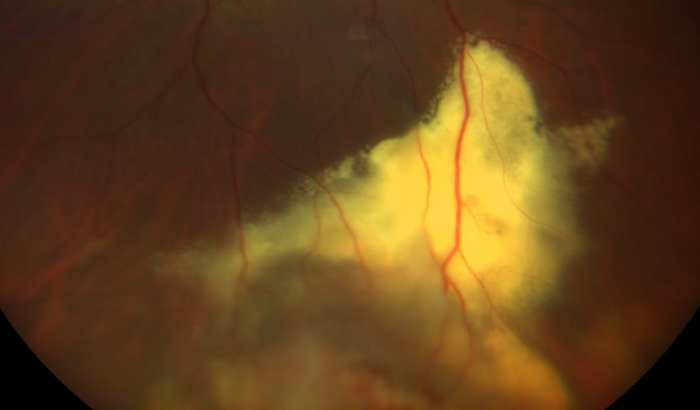

Venho através desta vakinha pedir a sua colaboração e oração para o tratamento que necessito realizar.A alguns dias comecei a sentir a minha visão embaçada, no dia 22 de setembro fui a uma consulta com o oftalmologista, onde o mesmo suspeitou de um tumor na parte inferior do olho. Foi marcado exame e uma nova consulta com especialista, onde foi confirmado a existência do problema. Com a benção de Deus o tumor é benigno, porém necessita de tratamento imediato, pois está em crescimento e descolando a retina. Daí partimos para a necessidade de realizar o procedimento de 4 aplicações injetáveis e laser para o tratamento, sendo q valor total do tratamento fica em 17.472,00, sendo inviável o levantamento deste montante para imediato tratamento. Por este motivo, peço a contribuição e oração de cada um.